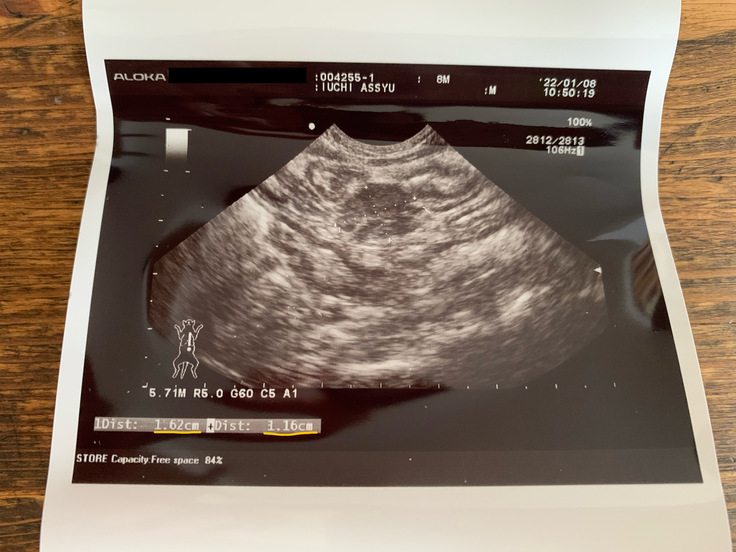

2022/1/8

治療開始から2週経過の定期受診・検査日。エコーの結果、腹水はゼロに!腹部のしこりも半分ほどの大きさに小さくなっていました!

次回診察・検査は4週後なので、お薬も4週(28日)分。

治療開始から15日が経ったこの日、診察・検査の結果でも改善が見られ、主治医からも経過は順調だと伝えられました。すごく安心した1日でした。1/8でアッシュは生後8ヶ月を迎えられました。無事にこの日を迎えられたこと、大変嬉しく思っております😌。